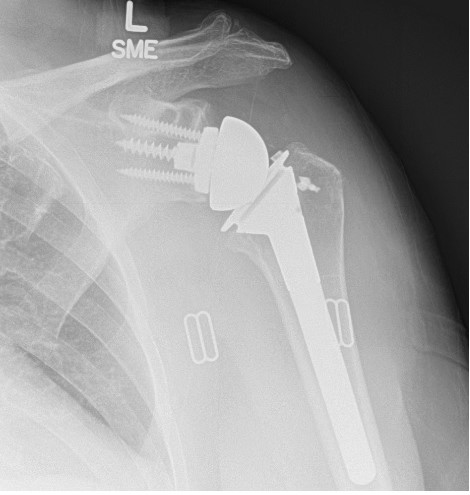

Pre-operative and post-operative xrays of a patient with rotator cuff tear arthropathy, treated with reverse total shoulder.

The reverse total shoulder was developed to help patients who have rotator cuff tears and shoulder arthritis. With a damaged rotator cuff, conventional anatomic total shoulder arthroplasty implants wear out too quickly. A reverse total shoulder involves replacing the ball and socket joints; however, the ball is moved to the "socket" side, and the "socket" is placed on the ball or humeral head side. This medializes and distalizes the center of rotation, allowing the deltoid muscle to raise the arm.

The reverse shoulder replacement uses a ball-and-socket joint where the ball is placed on the shoulder blade and the socket is placed on the top of the arm bone. This is reverse of our normal anatomy and is designed to make the deltoid muscle, the large shoulder muscle that caps the end of the shoulder, work better to make up for the deficiency of your worn out rotator cuff tendon.